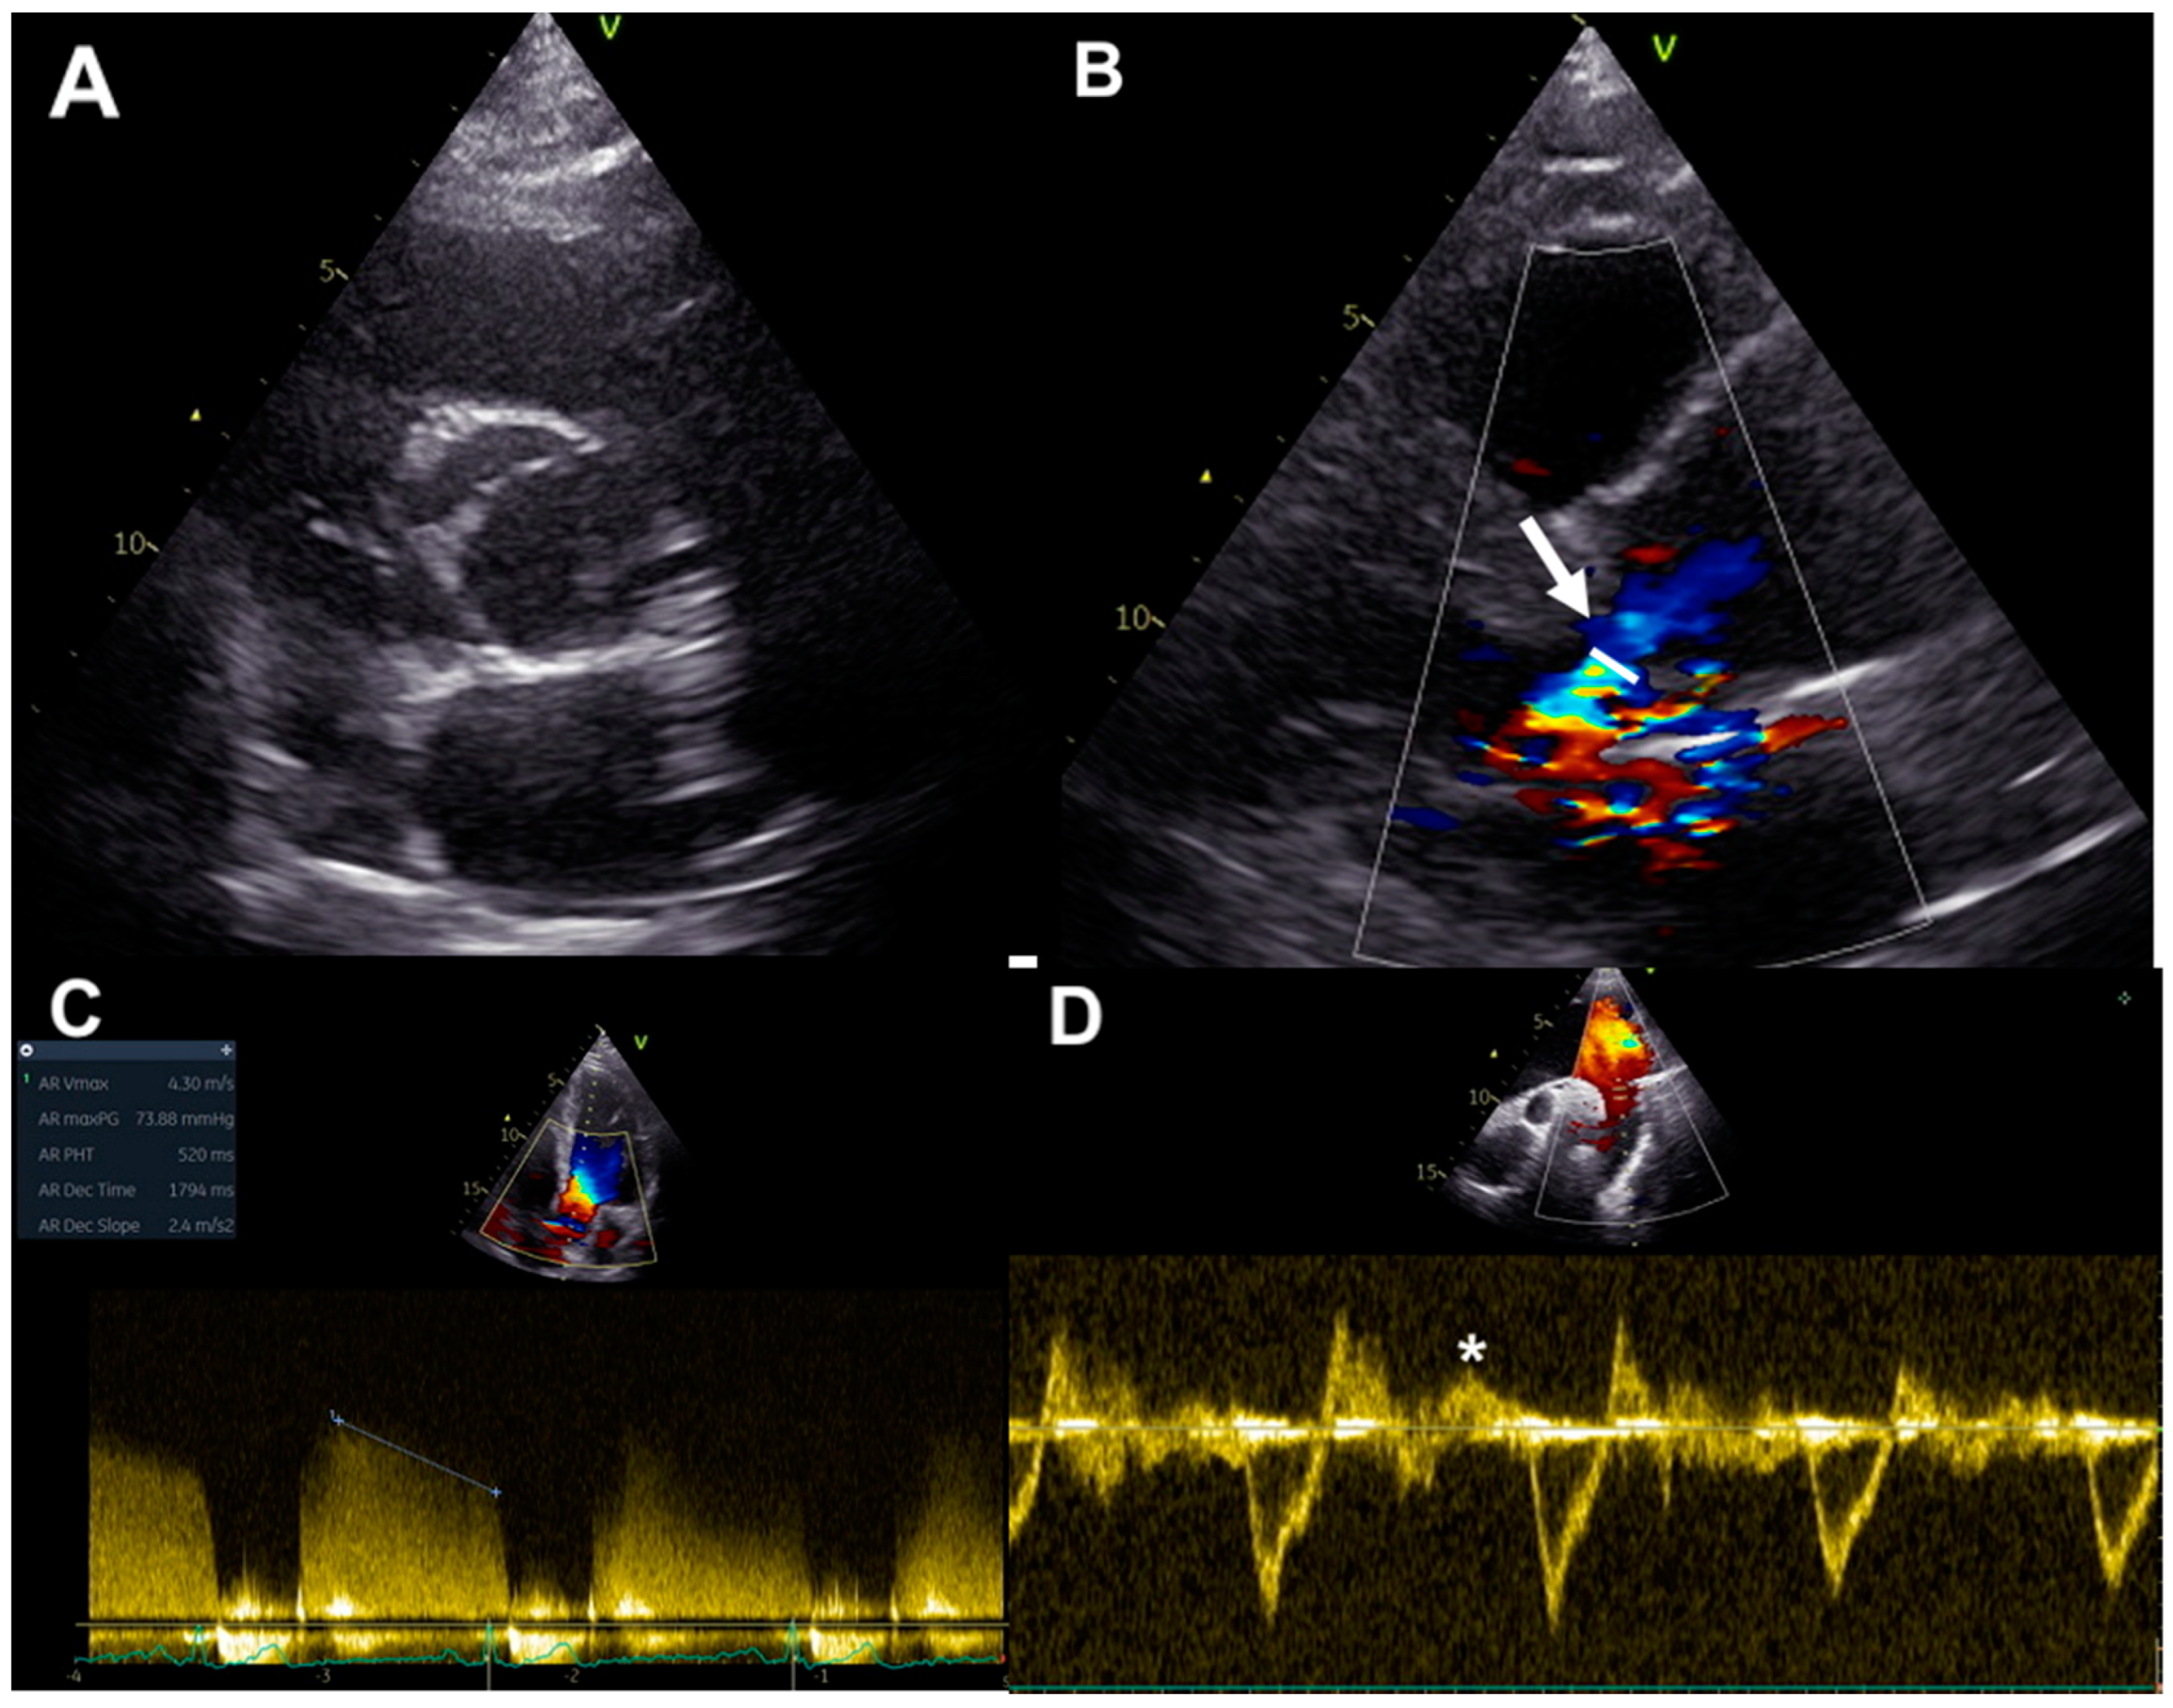

2.1. Qualitative and Quantitative Assessment

Ultrasound imaging permits the evaluation of cusps morphology, commissure variations, the presence and location of a raphe and root structure, providing information about aortic valve anatomy, and the mechanisms underlying valve regurgitation [23] (Figure 2A). Assessment of AR severity in BAV patients relies on color, continuous- and pulsed-wave Doppler measurements of the aortic regurgitant jet, together with the evaluation of left ventricular (LV) volumes and function, as for tricuspid valve patients [24]. Considering valve anatomy and the often eccentric and irregular shape of BAV jet regurgitations, some methodologies for the evaluation of AR severity grading are more advisable in BAV patients. Color flow Doppler imaging allows for visual estimation of the aortic regurgitant jet and gives information about jet eccentricity, a condition often present in BAV. The diameter and the cross-sectional jet area at its origin are semi-quantitative color Doppler indexes of AR severity. Since BAV patients often have an irregular shape of the regurgitant orifice, the ratio between the regurgitant jet width and LVOT diameter should not be used in this setting [23]. On the other hand, vena contracta width, representing the smallest flow diameter at the level of the aortic valve in LVOT, just below the flow convergence site, can be employed for the estimation of AR in BAV, being applicable even in eccentric regurgitation jets; AR is mild up to the limit of 3 mm and severe beyond the limit of 6 mm [25] (Figure 2B). Three-dimensional echocardiography was demonstrated to be a useful tool for the visualization of the actual shape of the regurgitant aortic orifice, and for the evaluation of the area of vena contracta, which correlates well with the effective regurgitant orifice area (EROA) [26]. Nonetheless, it has to be considered that the vena contracta assessment has the limitation to not be applicable in the presence of multiple regurgitation jets [24].

Furthermore, the proximal isovelocity surface area method can be used in BAV patients for the assessment of AR severity, allowing for estimation of EROA and regurgitant volume (RV). Using this methodology, AR severity grading is classified on the basis of EROA and/or RV, with severe AR defined for an EROA ≥ 30 mm2 or an RV ≥ 60 mL. However, this technique is limited by low feasibility in a big proportion of patients because of difficulty in detection of the flow convergence zone and possible interposition of valve tissue [24].

Continuous-wave Doppler-derived pressure half-time of regurgitant aortic jets could be used in BAV patients, but this technique requires an adequate Doppler angle for minimizing errors related to non-correct ultrasound beam alignment and this could be often difficult or not feasible, in particular in eccentric regurgitation jets. A pressure half-time less than 200 ms is associated with severe AR [24] (Figure 2C).

In addition, the assessment of the diastolic flow reversal in the descending aorta by pulsed-wave Doppler represents a strong parameter for evaluating AR severity: severe regurgitation is defined for holodiastolic flow reversal at velocities more than 20 cm/s [24] (Figure 2D).

Figure 2. BAV assessment by echocardiography: (A) valve anatomy in parasternal short axis; (B) vena contracta width in parasternal long-axis (arrow); (C) pressure half-time measurement in continuous-wave Doppler; (D) assessment of the diastolic flow reversal velocity in the descending aorta by pulsed-wave Doppler (*).